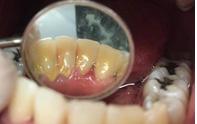

Se presenta un paciente de 22 años, quien refiere al interrogatorio no padecer ninguna enfermedad y no estar tomando ningún medicamento. En la evaluación clínica se obtuvo un promedio del índice IHOS regular 1.6 con presencia de bioplaca y sarro. El retiro del sarro que estaba en el área anterior de la superficie lingual de los

incisivos OD 31, 32, 41, 42 centrales y laterales inferiores fue con el CK6 pa el detartraje.

A la observación clínica a simple vista se vio la gingivitis y presencia de bioplaca en la mayoría de las superficies dentarias, por vestibular (Figura 5). El sarro localizado en los órganos

Figura 3. Inicio de detartraje y retiro del sarro. Figura 4. Final de paciente.

A B

dentarios incisivos centrales 31, 41 y laterales inferiores 32 y 42 en zona lingual, en la eliminación de las manchas extrínsecas (Figura 6).

Comparación inicio y final (Figura 7) con la eliminación del sarro de las superficies linguales de los OD de 32 al 42. El paciente fue citado para revisión en 6 meses.